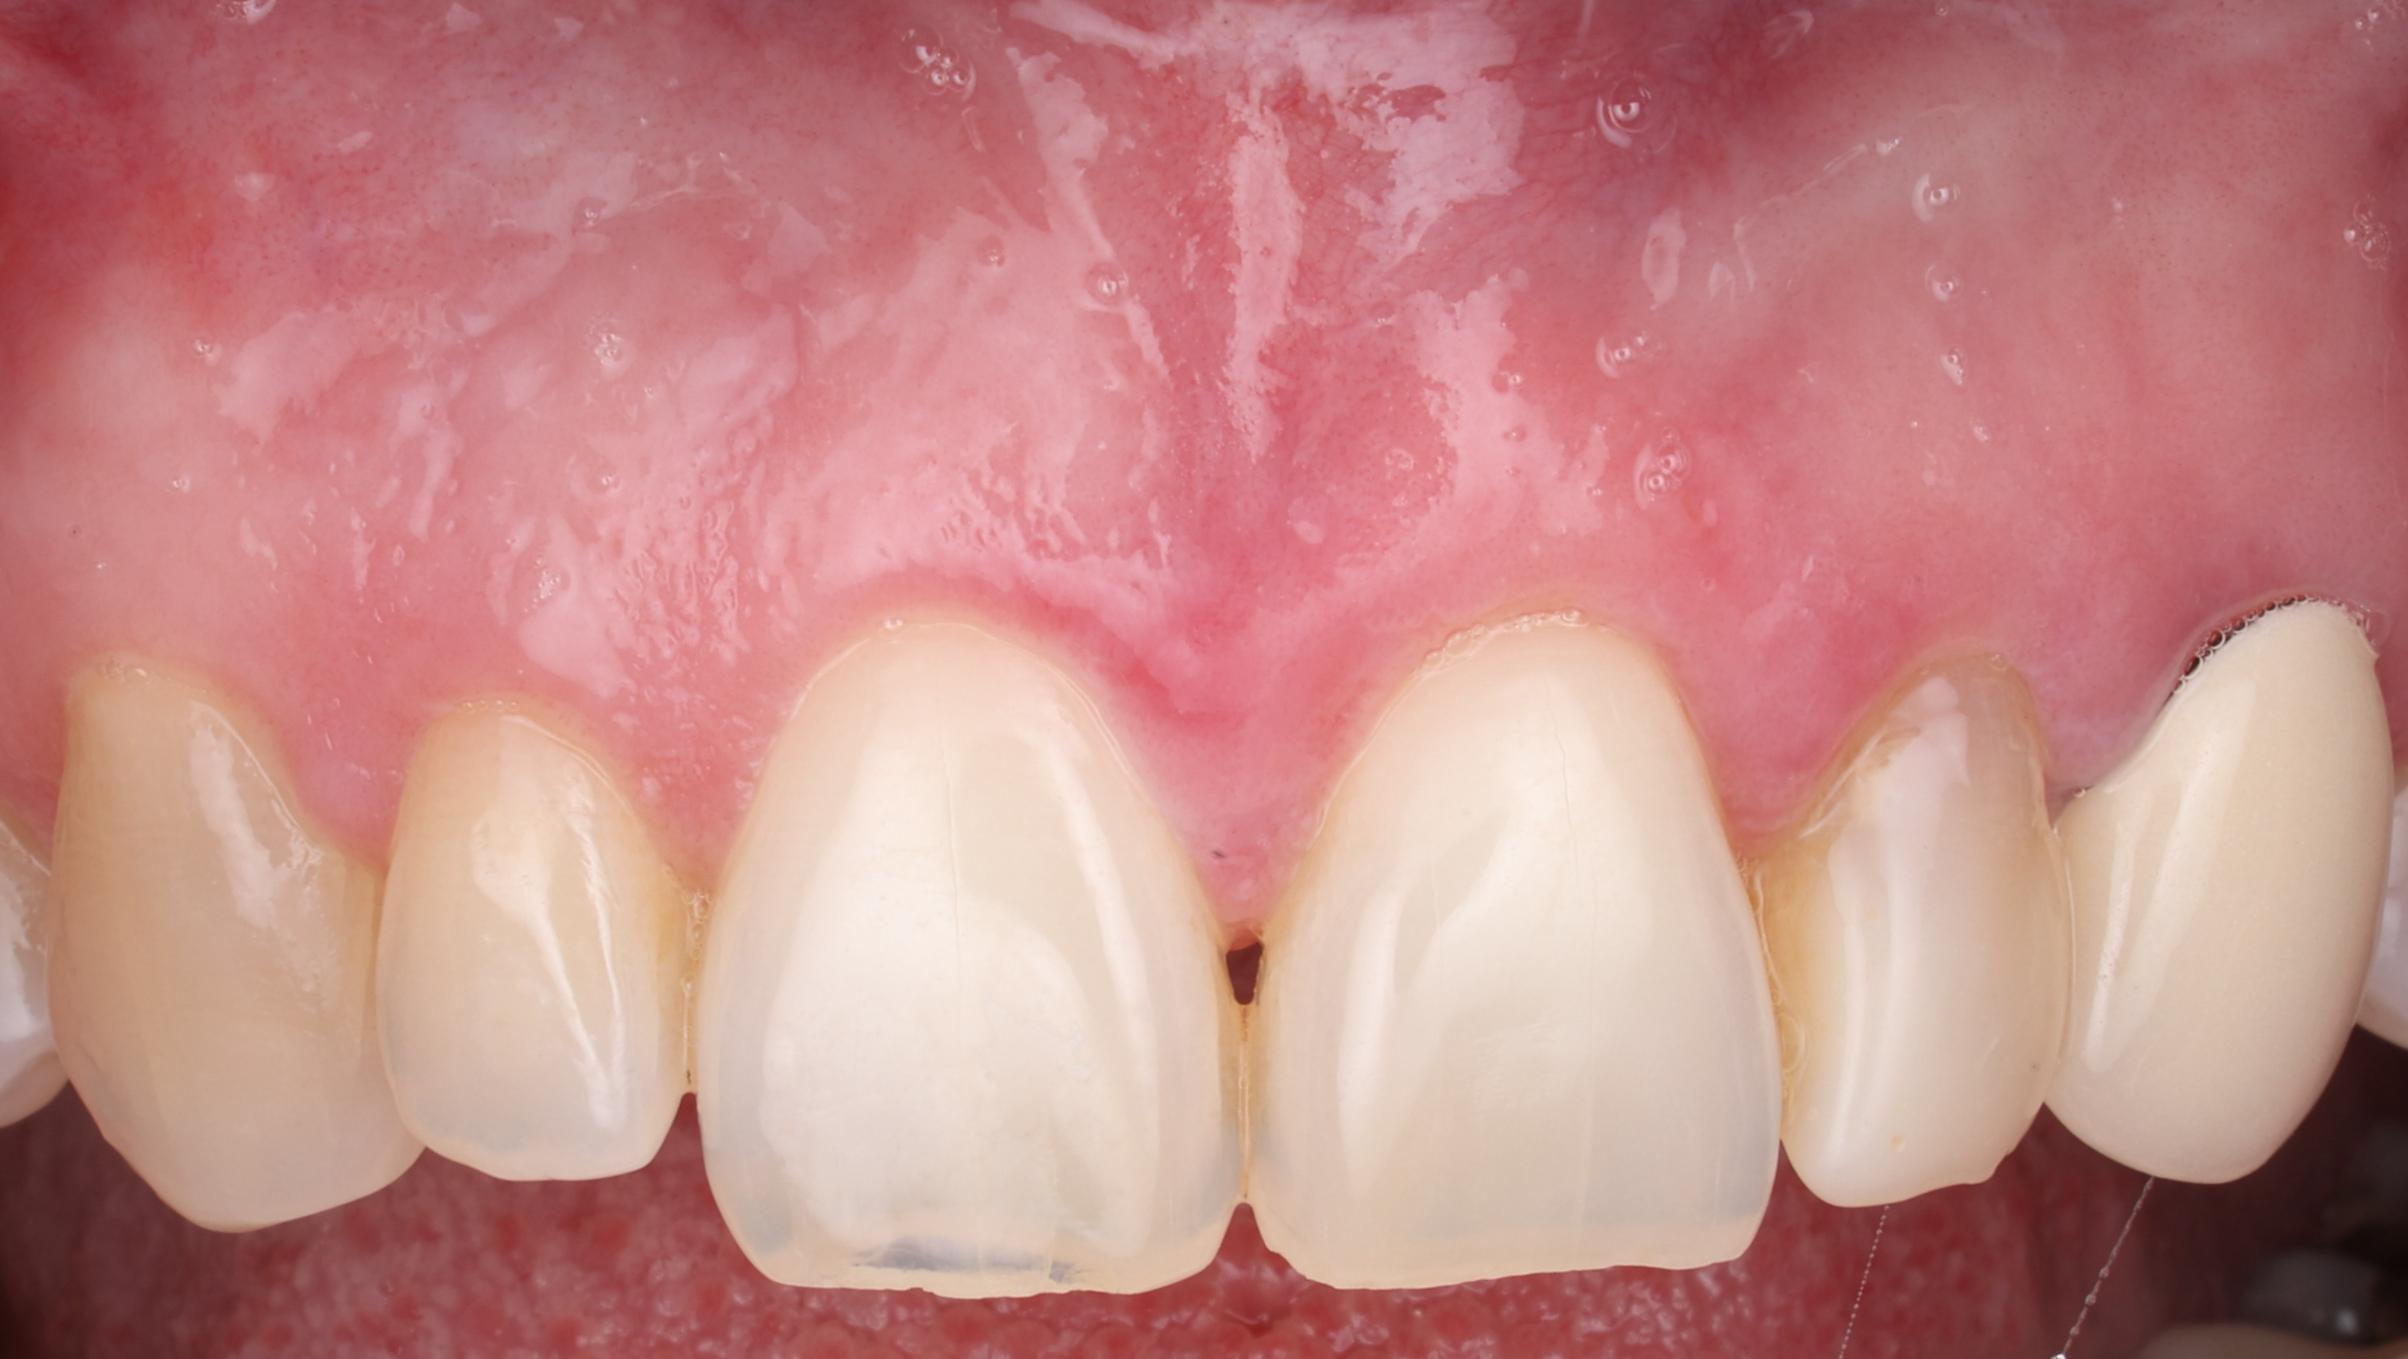

Esthetic Crown Lengthening

Before After

Before Image